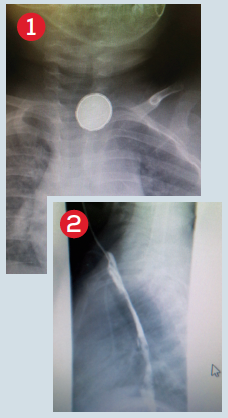

Photos courtesy of Cindy Nielsen, MD